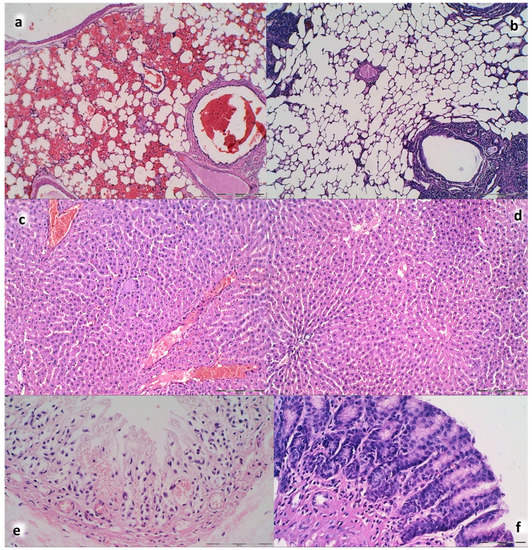

3.9. Histology